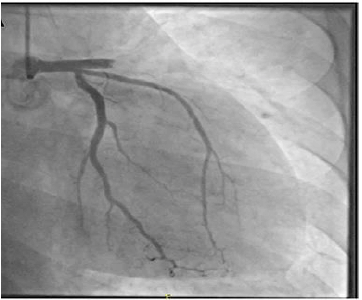

A coronariografia acima é compatível com a seguinte emergência cardiovascular:

O caso clínico a seguir refere-se a questão.

Mulher de 60 anos, sem comorbidades, relata dor torácica retroesternal em aperto de início há 90 minutos, que começou após ser informada do falecimento de seu irmão.

Ao exame: taquidispneica em ar ambiente, sudoreica, corada, acianótica. FC: 120 bpm; PA: 118 x 64 mmHg. MVUA com crepitação até os 2/3 superiores bilateralmente. RCR em 3 tempos (B3), bulhas normofonéticas, sem sopros ou turgência jugular patológica a 90°. O restante do exame físico foi normal. ECG de entrada com supradesnível de 2mm do segmento ST de V1-V4. Coronariografia de urgência não mostrou obstruções, mas a ventriculografia revelou disfunção sistólica moderada do ventrículo esquerdo, com acinesia antero-apical e hipercinesia das regiões basais.

Considerando o quadro acima, assinale o diagnóstico mais provável.